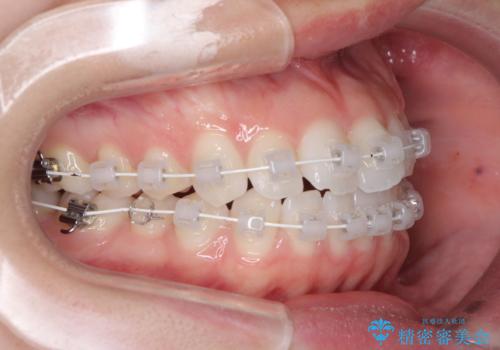

- 矯正装置

- 審美装置

- 海外留学を前に上下のデコボコと奥歯の咬み合わせを改善したいとのことで来院された患者様です。

期間が限られていたため、ワイヤー装置による矯正治療を行うこととしました。